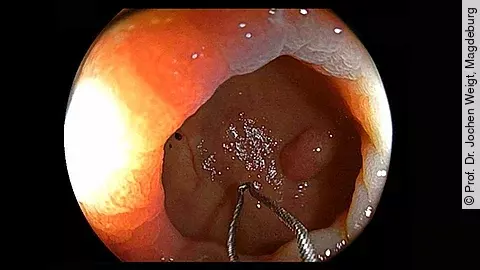

Mit dem neuen Videoformat „Drei Fragen an…“ starten wir eine Interviewreihe mit führenden Expertinnen und Experten der Medizin. Den Auftakt macht Prof. Dr. Martin Storr, Facharzt für Innere Medizin und Gastroenterologie und Leiter des Zentrums für Endoskopie in Starnberg.